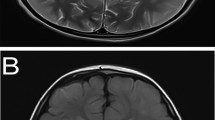

Rat pups were injected at postnatal day 0 with a single bolus of 2.5 μmol/g body weight GA into the cisterna magna. This treatment induced tonic–clonic convulsions that lasted up to 15 min after injection and were followed by 20–30 min hypotonic phases (Olivera et al. 2008; Olivera-Bravo et al. 2011). 80 % of the rats injected with GA survived without showing any gross difference regarding to the age-matched controls. The analysis of postnatal myelination was performed in the striatum and corpus callosum at 12, 21, and 45 days post-injection (DPI). GA-injected animals showed ~50 % decreased content in striatal myelin through 12DPI to 45DPI compared to respective controls (Fig. 1a, b). As myelination progressed with age, myelin-positive areas associated with axonal bundles in GA-injected pups were smaller and more condensed than controls (Fig. 1b). In contrast, myelination in the corpus callosum was unaffected by GA administration at all ages (Fig. 1c, e). When myelinated areas were stained with the more sensitive probe Fluoromyelin, the GA-induced reduction of myelinated areas oscillated between 25 and 30 % through 12DPI to 45DPI, with respect to controls (Fig. 2). The probe also evidenced the fragmentation and compaction of axonal bundles at 45DPI (Fig. 2a). Altered myelinated areas in GA-animals were also confirmed by the fragmentation and fading of the LFB turquoise lipid staining (Fig. 2b). The comparative quantitation made at all ages and with all markers confirmed significant GA-induced myelination failure in the striatum (Fig. 2c).

Effect of icv GA on myelination of striatal and corpus callosum axons Panoramic (a) and higher magnification (b) images of Sudan III histochemistry of transversal brain sections showing positive myelinated areas at 12, 21, and 45 days after icv GA administration (DPI) evidencing long-term decrease in the striatum of GA pups related to age-matched controls. The inset shows the area imaged. Calibration bars = 200 and 60 μm for (a) and (b), respectively. c Corpus callosum Sudan III positive staining evidencing preserved myelination at all ages analyzed. Scheme shows the area analyzed, that is close to the cingulum. Calibration bar = 60 μm. d Fluoromyelin staining showing that GA-animals preserved corpus callosum fibers at 45DPI. Calibration bar = 30 μm. e Quantitation of the intensity of SIII positive signals in corpus callosum (cc) and striatum (st) from 5 to 7 GA-injected animals as compared to 5–7 controls denoting significant differences only in the striatum (*p < 0.05). Data are the mean ± SD